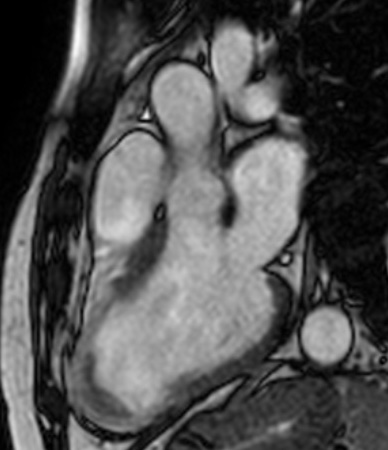

Ischemic cardiomyopathy involving LAD and partly LCX territory

There is mild hypertrophy of the basal and mid-myocardial inter-ventricular septum (IVS). It measures 11 mm in mid segment (diastole) and 14 mm in systole.

There is also mild thickening of the free wall of the left ventricle in basal and mid cavity regions.

There is severe thinning of the apical myocardium.

There is focal T2 hypointense non enhancing soft issue seen in apical region of left ventricle most likely representing apical thrombus.

There is transmural enhancement seen in the apical, apical anterior, apical septal, apical inferior,  mid-ant septal, mid inf-septal segments ( segments17, 13,14,15,8,9). It probably represents scar tissue of non viable myocardium.